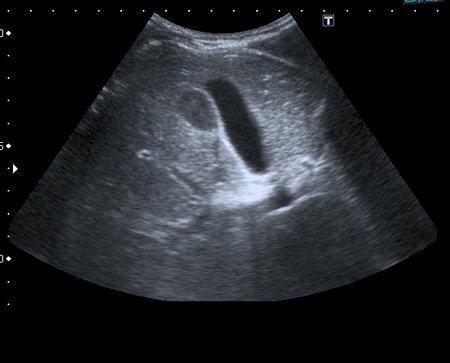

На УЗИ рядом с желчным пузырём определяется овоидное образование солидной струкутры с чёткими контурами.

При ЦДК кровоток в образовании не регистрировался, свободной жидкости в брюшной полости не было.

Предположил наличие удвоения желчного пузыря, с этим заключением пациент исчез из поля зрения.